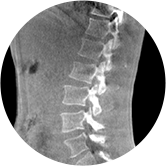

腰椎